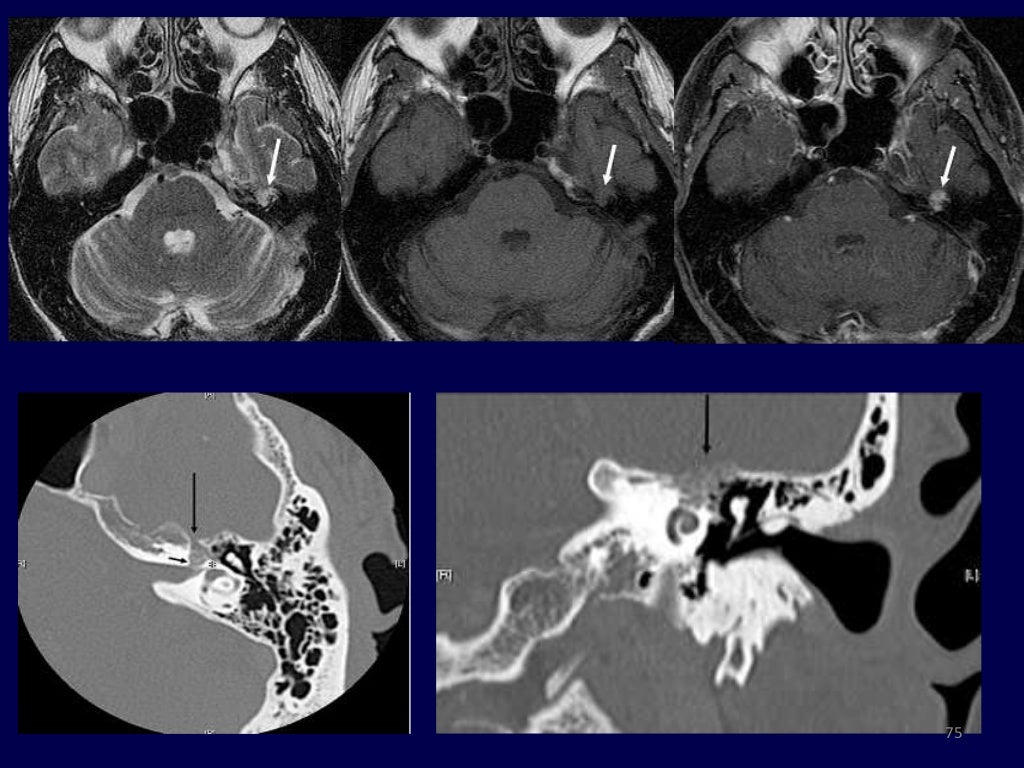

From www.researchgate.net

resonance of the middle ear. (A) Fluidattenuated inversion Resonance Ear mri of the inner auditory canal, middle ear, and labyrinth is complex and requires a detailed knowledge of the regional anatomy, the most common pathologic entities, and the expected postsurgical findings. the hearing is the process by which sound vibrations transform from the external environment. The etiology of many complaints in and around the ear is. ear. Resonance Ear.

Axial resonance imaging (MRI) scans of the middle ear. (a) T1 Resonance Ear The etiology of many complaints in and around the ear is. mri of the inner auditory canal, middle ear, and labyrinth is complex and requires a detailed knowledge of the regional anatomy, the most common pathologic entities, and the expected postsurgical findings. ear and the concepts of acoustic impedance and resonance. the hearing is the process by. Resonance Ear.

Axial resonance imaging (MRI) scans of the middle ear. (a) T1 Resonance Ear mri of the inner auditory canal, middle ear, and labyrinth is complex and requires a detailed knowledge of the regional anatomy, the most common pathologic entities, and the expected postsurgical findings. the hearing is the process by which sound vibrations transform from the external environment. ear and the concepts of acoustic impedance and resonance. The etiology of. Resonance Ear.